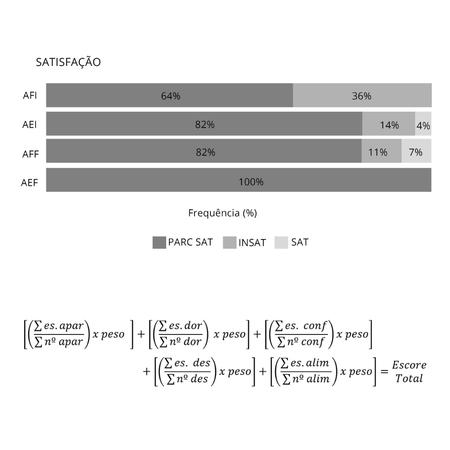

Objetivo: Este estudo teve como objetivo comparar o impacto do tratamento com alinhadores estéticos versus aparelhos fixos convencionais na vida cotidiana de pacientes ortodônticos durante os primeiros seis meses e nos últimos seis meses de tratamento. Métodos: O estudo envolveu 112 pacientes adultos, divididos em quatro grupos. Todos os participantes responderam ao questionário “Dental Impacts on Daily Living” (DIDL), que incluía 36 perguntas e abrangia cinco domínios, incluindo...

Objective: This study aimed to compare the impact of treatment with clear aligners versus conventional fixed appliances on the daily lives of orthodontic patients during the first six months and the last six months of treatment. Methods: The study involved 112 adult patients who were divided into four groups. All participants completed the “Dental Impacts on Daily Living” (DIDL) questionnaire, which included 36 questions and covered five domains including appearance, pain, comfort,...